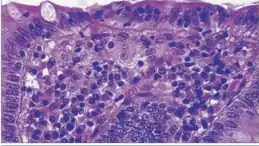

| A micrograph demonstrating cryptitis, a microscopic correlate of colitis. H&E stain. | |

An important investigation in the assessment of colitis is biopsy. A very small piece of tissue (usually about 2mm) is removed from the bowel mucosa during endoscopy and examined under the microscope by a histopathologist. It can provide important information regarding the cause of the disease and the extent of bowel damage.